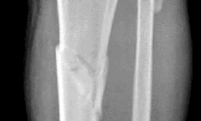

Question 8:

A 13-year-old boy with a BMI in the 95th percentile presents with a 2-month history of vague left knee and thigh pain. On physical examination, he has an obligate external rotation of the left hip with passive hip flexion. Radiographs confirm a slipped capital femoral epiphysis (SCFE). Which of the following best describes the anatomic displacement of the femoral metaphysis relative to the epiphysis in this condition?

Correct Answer: Metaphysis displaces anterior and superior

Explanation:

In Slipped Capital Femoral Epiphysis (SCFE), the proximal femoral epiphysis remains relatively secure in the acetabulum while the femoral neck (metaphysis) displaces. Because the mechanical axis of weight-bearing forces acts anteriorly and superiorly on the proximal femur, the metaphysis translates anteriorly and superiorly. Clinically and radiographically, this makes the epiphysis appear to have slipped posteriorly and inferiorly relative to the neck. Therefore, the metaphysis moves anteriorly and superiorly.